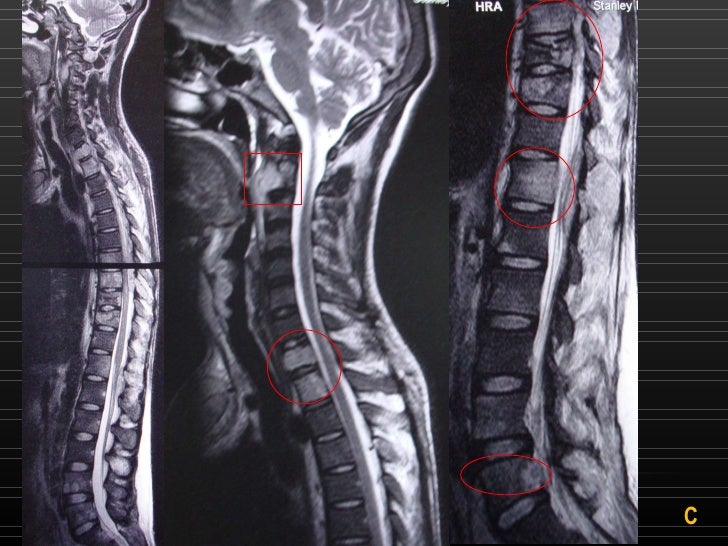

MRI Collapsed Vertebral Bodies Concertina Collapse Of Vertebrae Later findings include vertebral collapse described by seddon as “concertina collapse” because of its resemblance to an accordion. Later findings include vertebral collapse, described by seddon, as “concertina collapse” because of its resemblance to an. Bone destruction will eventually lead to anterior wedging and kyphosis or concertina collapse of single vertebral body. The adjacent discs are removed using a curette.. Concertina Collapse Of Vertebrae.

Spinal Cord Tuberculosis

(Case 1) a Sagittal T1 and T2weighted images showing collapsed... Download Scientific Diagram Concertina Collapse Of Vertebrae The adjacent discs are removed using a curette. Soft tissue swelling and its. Later findings include vertebral collapse, described by seddon, as “concertina collapse” because of its resemblance to an. Commonest presenting symptom of pott’s spine is back pain. Bone destruction will eventually lead to anterior wedging and kyphosis or concertina collapse of single vertebral body. The paradiscal type is. Concertina Collapse Of Vertebrae.